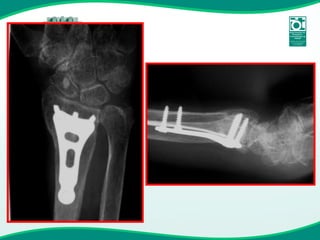

Fixação Interna

Placa DVR

Placa Ortogonal

Placa Locon-T (Wright) LCP  ORTOGONAL